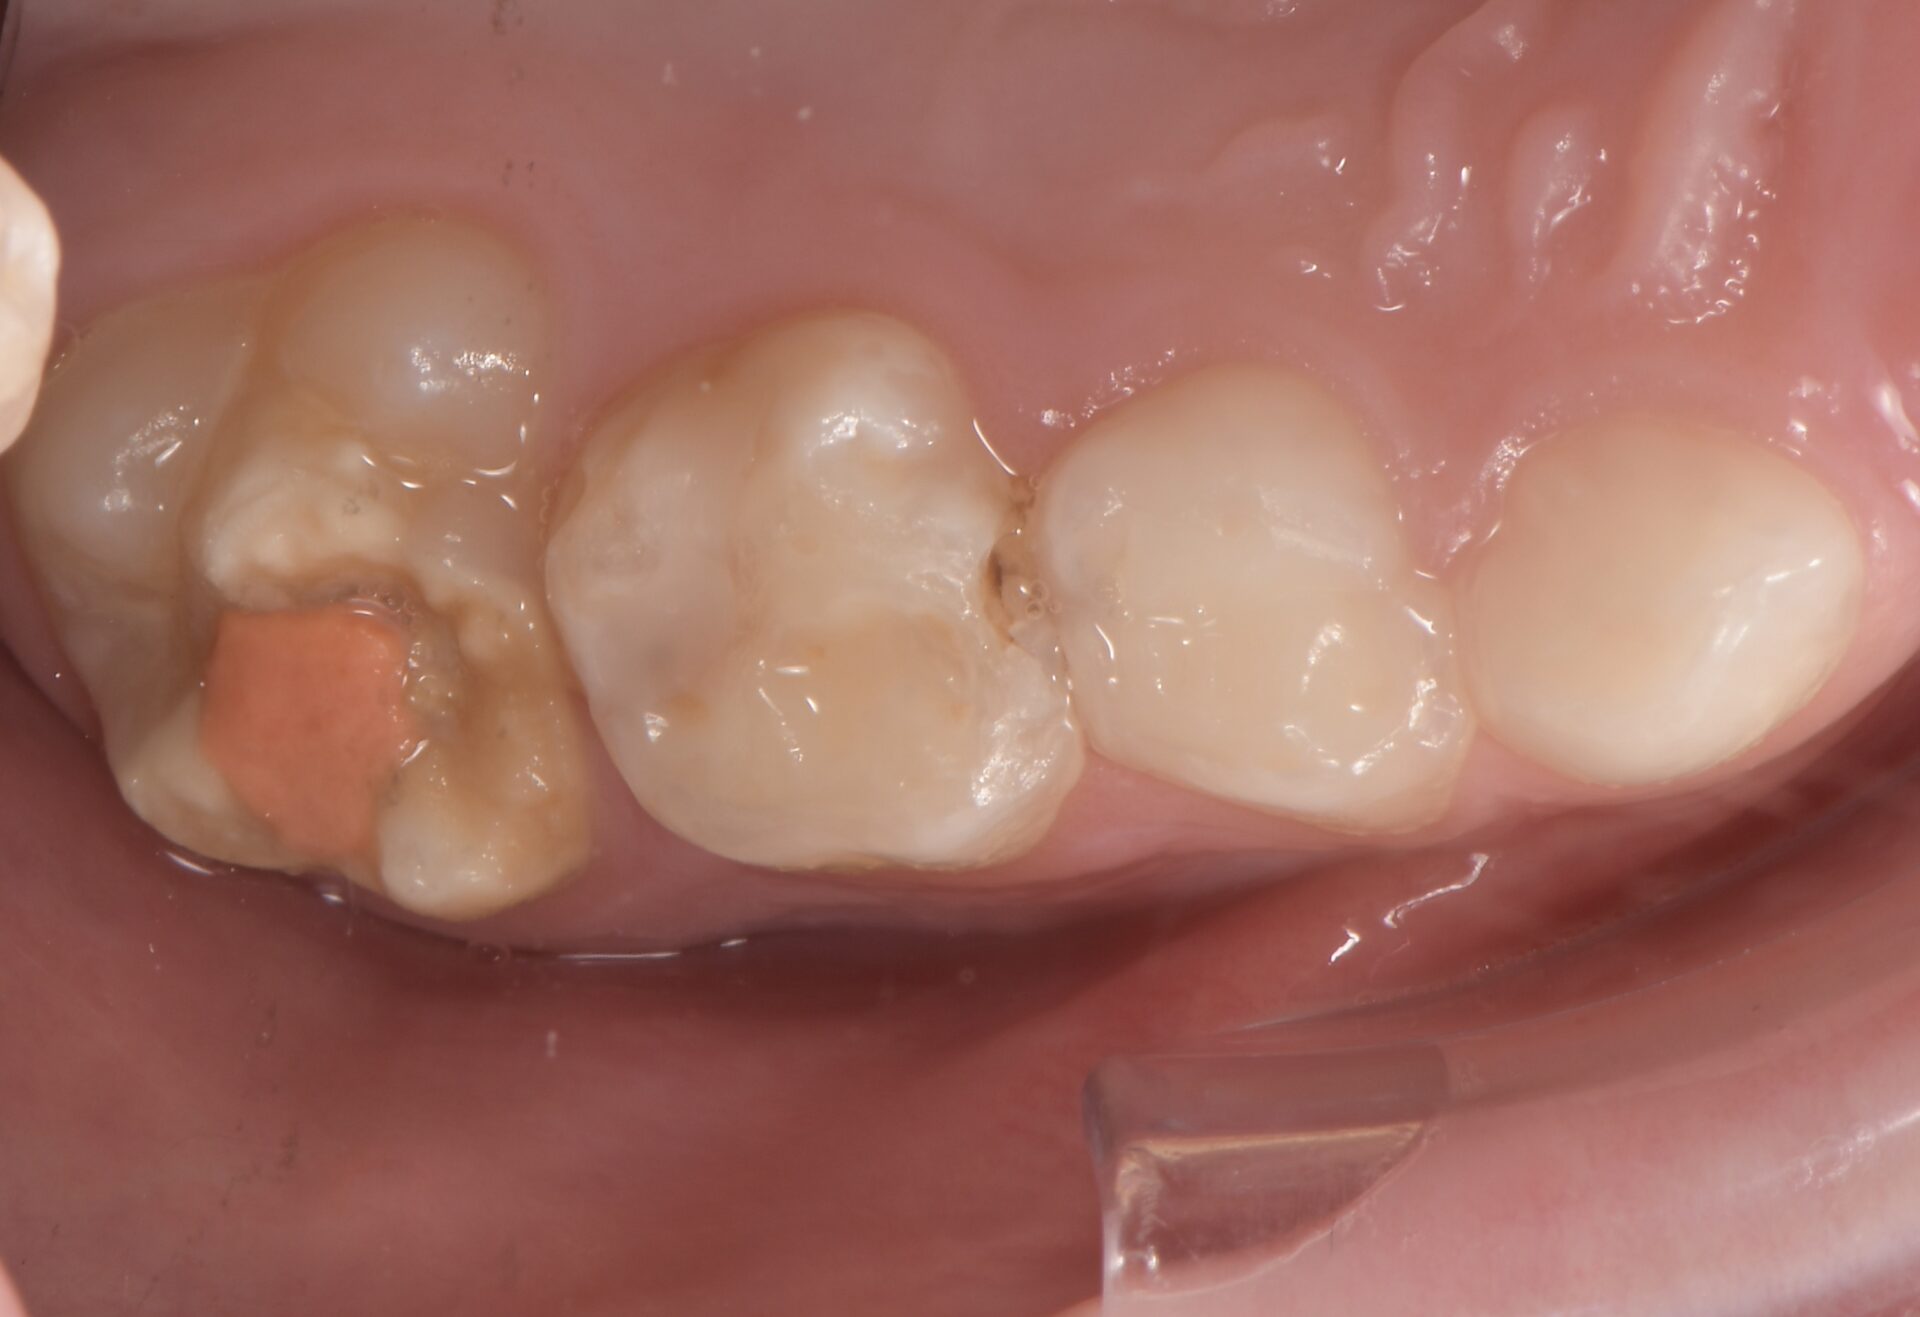

Le congrès de l’EAPD (Académie Européenne d’Odontologie Pédiatrique) a défini des critères de diagnostic en 2003. A savoir des opacités délimités, des fractures post-éruptives, des restaurations atypiques ainsi que que des extractions des molaires. (3) Le diagnostic différentiel doit surtout s’établir entre des amélogénèses imparfaites et des hypominéralisations d’origine traumatique pour les dents antérieures. Cliniquement, les dents vont présenter des colorations blanches ou brunes opaques sur une partie ou sur toute la surface de la dent (Figures 1-2-3-4).

Pour les secteurs postérieurs, en fonction du délabrement tissulaire (PEB ou consécutif à une atteinte carieuse), on optera pour des restaurations directes en composite (Figures 11-12).

formation dentaire pédodontie Figure 11.

formation dentaire pédodontie Figure 12.

ou indirectes de type onlay en céramique (Figures 13-14-15).

Figure 3-4 : Molaires atteintes de MIH (HSPM + MIH pour la figure 3)

Figures 11-12 : Taitement postérieur par résine composite.

Figures 13-14-15 : TraitemEnt postérieur par onlay céramique.